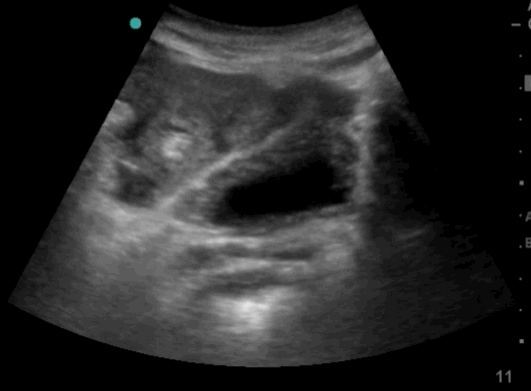

- The ultrasound clips below provide examples of examinations with and without free fluid in relation to the bladder. The views are obtained from the lower part of the abdomen, just above the symphysis pubis. Both longitudinal and transverse views are used to assess the presence of free fluid, which, if present, appears above or cranial to the bladder. Intraperitoneal fluid appears as black hypoechoic or anechoic areas surrounding the bladder and intestines. A full bladder improves visualization, serving as a helpful reference for evaluating free fluid in the peritoneum.